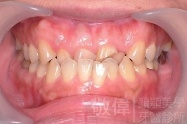

變臉矯正,原來戽斗妹跟大歪臉變成自信正妹

經由本院3D數影X光影像儀分析、與3D齒顎顏矯正技術,再配合口腔顎面正顎專科醫師施以正顎手術治療,雙方共同合作,使患者臉部外觀有很好的改善,大歪變小歪,產生了天南地北的大改變,她的人生也整個變得不一樣。

因為矯正與正顎手術的配合,使「戽斗妹」變成了「陽光正妹」,完全的改變了她的人生,在面對各種場合、與人交際都散發出自信微笑。所以,奉勸家長,如果小朋友有臉顎畸型的問題,應該考慮配合做這種簡單、安全、有效的正顎手術。

「3D齒顎顏矯正」,不止矯正您的牙齒,也會改變您的人生。「治療前」和「治療後」出社會的人生際遇一定會截然不同。